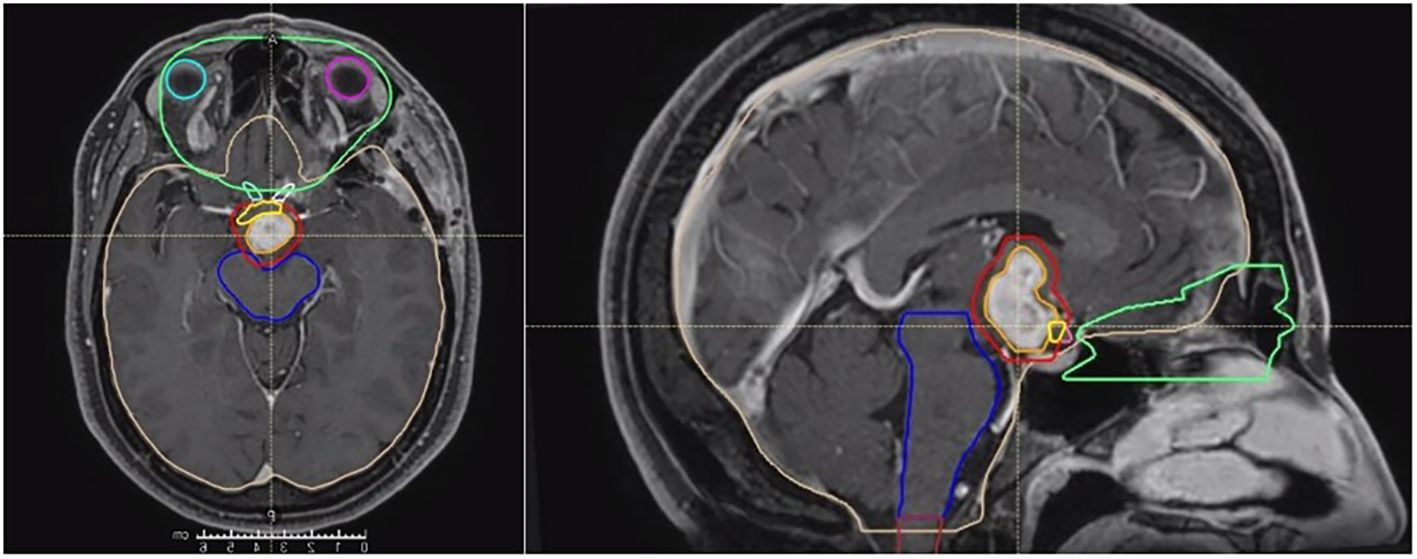

Background Chordoid glioma is a rare Grade II WHO brain tumor located in proximity of the third ventricle. Less than 100 cases are reported in the literature and surgery represents the main treatment option. Due to the typical location, complete surgical resection is uncommon, but the role of adjuvant radiotherapy is controversial. Methods Starting from a case report, we performed a literature review focused on the potential role of adjuvant radiotherapy for chordoid gliomas, reporting data on patients'characteristics, surgical approach and extent resection, radiotherapy technique and dose, and clinical outcomes. Results A total of 18 patients in 14 studies were identified, with a prevalent use of stereotactic treatments over conventional external beam radiotherapy, with doses respectively ranging between 11.5-18 Gy and 45-59.4 Gy, for a median time of local control of 26 months. Five patients developed disease recurrence after a median time of 22.4 months. In the case of the present study, the patient received adjuvant conventional radiotherapy (59.4 Gy/33 fx) is alive after 12 months of follow-up with no major side effects Conclusions From the available evidence, modern radiotherapy could be considered as a therapeutic tool able to conjugate less invasive surgical procedures with improved local control, thus reducing the risk of severe post-operative complications. Larger studies with longer follow-up are mandatory.